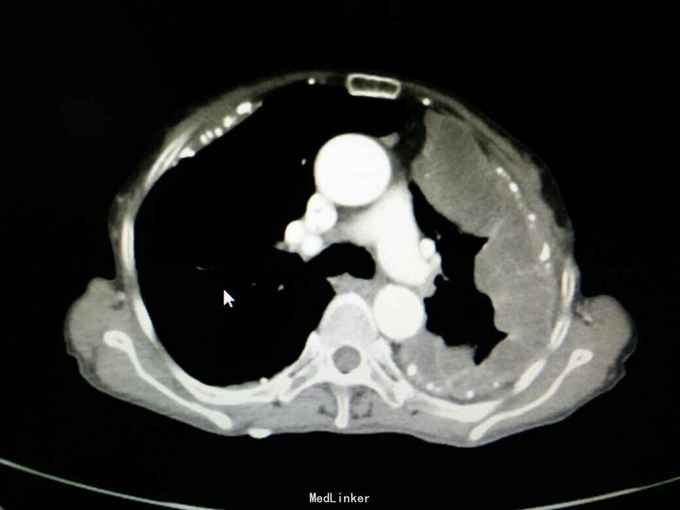

查体:神志清,精神可,生命体征平稳。两肺呼吸音粗,未闻及干湿性啰音。 辅查: 血气分析:PH7.43, 二氧化碳分压43mmHg, 氧分压77mmHg, 氧饱和度95%。 血常规:WBC7.5x10∧9/L, NE77.8%, Hb132g/L, plt231x10∧9/L。 尿常规,粪便常规,凝血功能,肿瘤标志物,CRP, 免疫功能,肝肾功能电解质无明显异常。 痰培养,痰找抗酸杆菌阴性。 心电图无明显异常。 心脏彩超:主动脉瓣局部退行性变,左室舒张功能减退,轻度肺高压。 腹部B超无异常。 胸部增强CT:双侧多发胸膜斑,左侧胸膜弥漫结节状及团块形成,考虑石棉肺伴左侧胸膜继发性恶性间皮瘤可能。

入院诊断:左侧胸膜肿物:胸膜间皮瘤? 诊治经过:予对症支持治疗,行CT引导下胸膜活检 病理:结合免疫组化和临床病史,符合恶性间皮瘤。 治疗:患者明确诊断后予化疗前预处理,择期行培美曲塞+铂类化疗